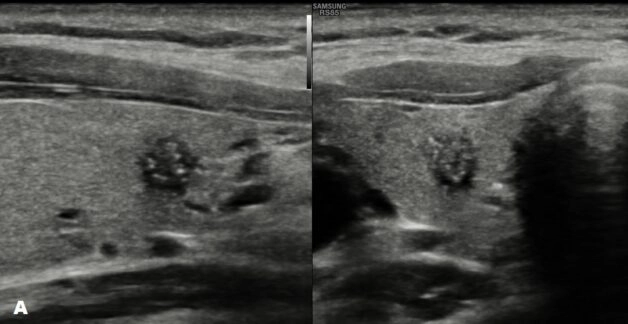

Hình ảnh tuyến giáp có nhân giảm âm

Siêu âm tuyến giáp thường là bước đầu tiên trong việc xác định sự có mặt của nhân giáp. Siêu âm này sử dụng sóng siêu âm để tạo hình ảnh tuyến giáp và khối u, giúp bác sĩ xác định kích thước và vị trí của nhân giáp giảm âm.